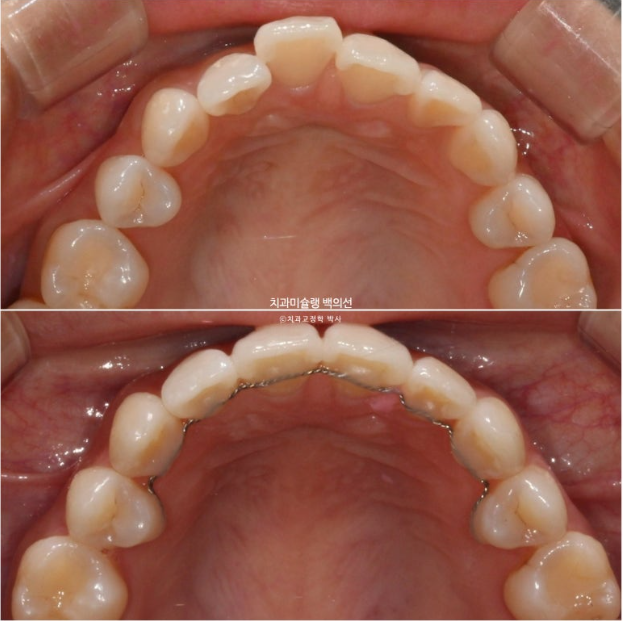

25년 2월 교정치료를 위해 온 환자분입니다.

오래 전 발치교정을 했는데 유지관리 단계에서 다시 틀어져 버렸습니다.

그 당시 원장님이 철사유지장치는 안해주고 뺏다꼈다 하는 유지장치만 줬다고 합니다.

재교정을 해서 고치고 싶은 것은 튀어나온 위 앞니와 아래앞니의 블랙트라이앵글

앞니 하나가 들려있어요.

중절치 하나가 많이 나와있습니다.

아랫니도 약간의 배열 불규칙이 보입니다.